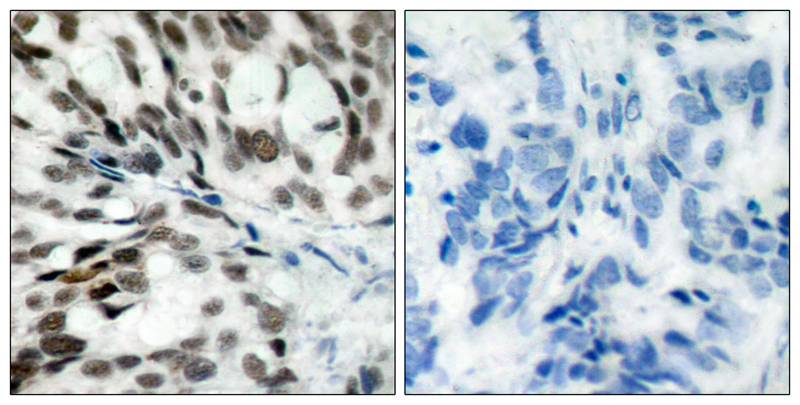

分类: 科研抗体货号: P41331别名: pRb应用: WB,IHC反应种属: Human,Mouse,Rat